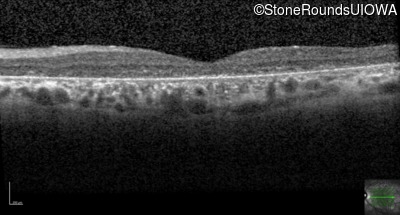

Optical Coherence Tomography - Left - 10/300 sc

Exemplar / OCT Stack

OCT Stack